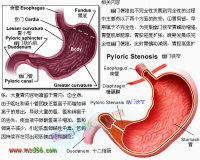

胃可分为四个部分:贲门部、胃底部、胃体部和胃窦部。胃的入口为贲门,出口为幽门。胃窦指的是幽门与胃角切迹平面之间的部分。胃窦炎好发于30岁以上的男性,表现为上腹部饱胀,隐痛或剧痛,常呈周期性发作,可伴有嗳气、反酸、呕吐、纳差、消瘦等,慢性胃窦炎还可表现为厌食,持续性腹痛,失血性贫血等。胃窦炎病变多局限于粘膜肌层,亦可蔓延至肌层和浆膜层。胃窦粘膜表现为水肿、充血,炎性细胞浸润和纤维组织增生,其中以粘膜下层最为明显。此外,当有粘膜糜烂,腺体萎缩与肠腺增生,胃窦炎很少单独存在,常与消化性溃疡或胃癌同时存在,因为胃窦炎与萎缩性胃炎、胃溃疡、胃癌关系密切,应引起我们的高度重视。

本症与精神因素关系密切,情绪波动或恐惧紧张时,可使症状加剧。副交感神经系统兴奋时也易发作。有些胃窦炎患者,上腹疼症状与十二指肠球部溃疡相似,慢性胃窦炎容易误诊为胃窦癌,需做胃镜检查来区别。

1、胃窦激惹,表现为幽门前区经常处于半收缩状态,不能象正常那样在蠕动波将到达时如囊状,但能缩小至胃腔呈线状。

2、粘膜纹增粗、紊乱,可宽达1cm左右,胃窦粘膜纹多呈横行,胃壁轮廓呈规则的锯齿状,锯齿的边缘也甚光滑。

3、当病变发展至肌层肥厚时,常表现为胃窦向心性狭窄,形态比较固定,一般可收缩至极细,但不能舒张,与正常段呈逐渐过渡或分界比较清楚。狭窄段可显示粘膜纹,多数呈纵行。